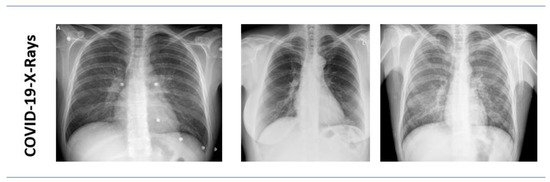

3.1.1. Kaggle COVID-19 Radiography Database

3.1.2. COVID-19 Chest X-ray Dataset by Joseph Paul Cohen

3.1.3. Data Distribution